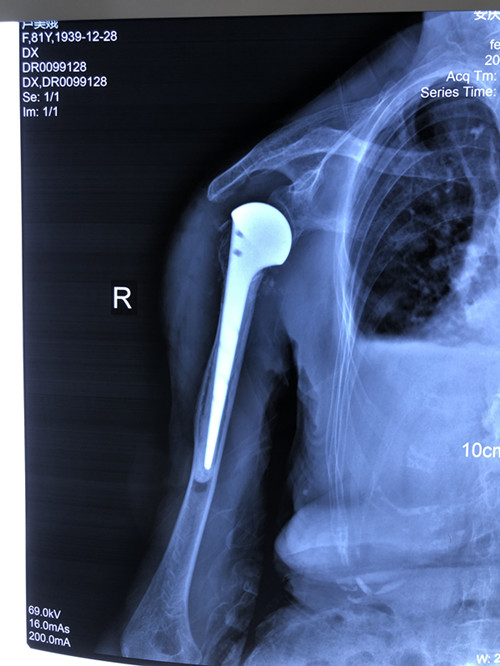

李老太是粉碎性骨折,情況較為嚴重,為恢復(fù)肩關(guān)節(jié)功能,石化醫(yī)院骨科副主任張明龍帶領(lǐng)團隊充分評估病情,與病人和家屬協(xié)商后,決定實施人工肱骨頭置換術(shù),在右肩安裝一個“人工肩關(guān)節(jié)”。

人工肱骨頭置換術(shù)是一個“精細活”,技術(shù)要求高、操作難度大,人工假體尺寸的選擇、安放的位置都很有講究。手術(shù)當天,張明龍主任帶領(lǐng)團隊僅用時一個多小時,就成功將“人工肩關(guān)節(jié)”植入患者體內(nèi)。